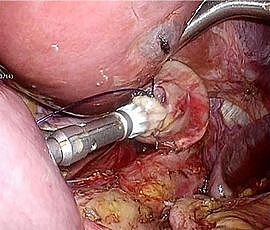

[胃がん] 手術:腹腔鏡下胃全摘術

手術画像